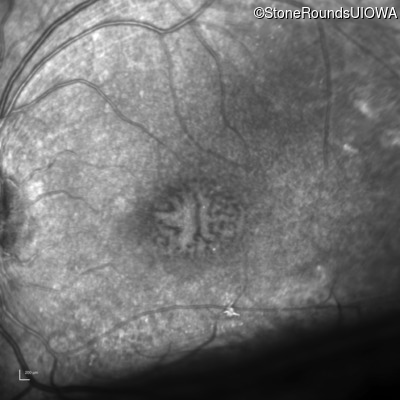

XL Retinoschisis (IIIB1)

Age at visit: 3 years

This 3 1/2 year old boy was noted to have a right esotropia 1 year earlier.

Diagnosis & molecular findings

Disease Gene Allele 1 variant(s) Allele 2 variant(s) Inheritance mode

XL Retinoschisis RS1 Ser221 Ins1aG   XL